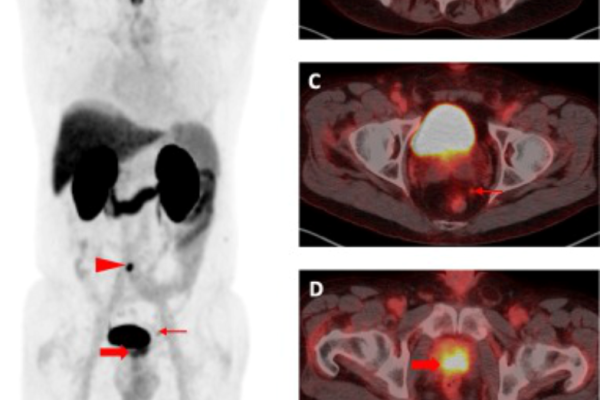

PSMA

68-Ga PSMA PET-CT is an advanced molecular imaging technique specifically designed for detecting prostate cancer. It targets the Prostate-Specific Membrane Antigen (PSMA), a protein that is highly expressed on prostate cancer cells. This scan offers exceptional sensitivity and accuracy, even at very low PSA levels, making it valuable for both initial staging and identifying recurrence. It also plays a critical role in guiding treatment decisions, especially for patients being considered for PSMA-targeted therapies.

Key Indications:

• Initial staging of high-risk prostate cancer

• Detection of biochemical recurrence after surgery or radiation

• Evaluation of metastasis before or during treatment

• Selection for PSMA-targeted radionuclide therapy